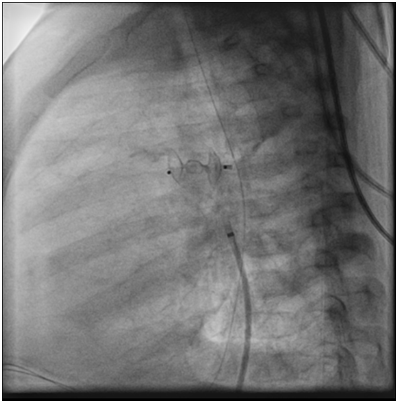

A catheter was easily passed percutaneously through the femoral vein into the pulmonary artery and aorta through the PDA. It was decided that to close the PDA with amplatzer ductal occluder type 2 size 4 by 6mm, and successfully closed (Figure 5) (Figure 6).

Figure 6 Angiogram: suitable device size without any leak.